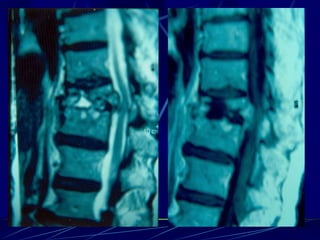

Φυματίωση της σπονδυλικής στήλης